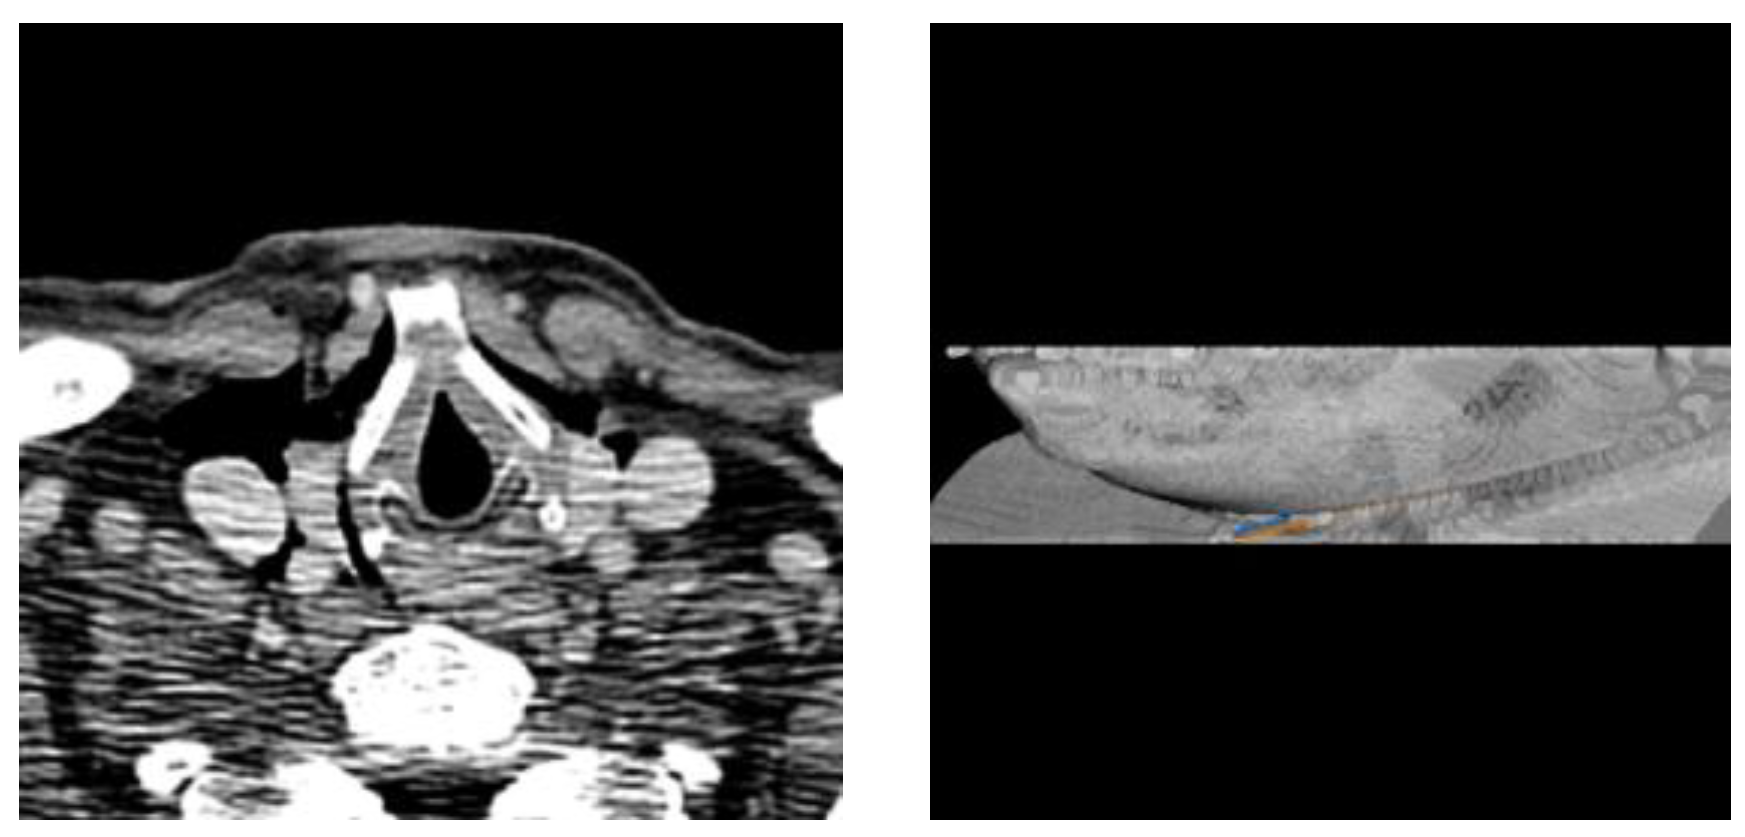

Automatic Needle Route Proposal in Preoperative Neck CT for Injection Laryngoplasty

- We propose the first automatic method to compute the optimal needle route in neck CT for TIL based on critical structure segmentation and minimal cost route search.

2.2. Critical Region Segmentation

2.3. Search Space

2.4. Optimal Needle Route Search

3. Experimental Results